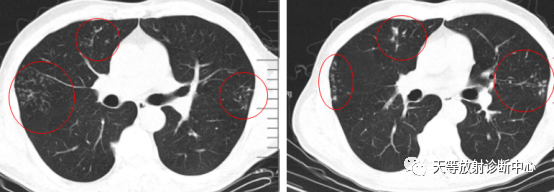

影像学表现:整体观察肺内多发病灶,散在分布,病灶的主要形态为:多发大小不等肺气囊、多发结节共同存在。

1、肺气囊大小不等,张力较大,圆形膨胀感强,周围可见大小不等结节影;

2、病灶主要沿支气管血管束方向分布,部分病灶达到胸膜下;

3、支气管间质增厚;

4、结节影大小不等,小的呈树芽征堆积,大的部分到达胸膜小,具有糊墙征,性格较温和。仔细观察病灶呈四边形、多边形,边缘刀切感,边界模糊。